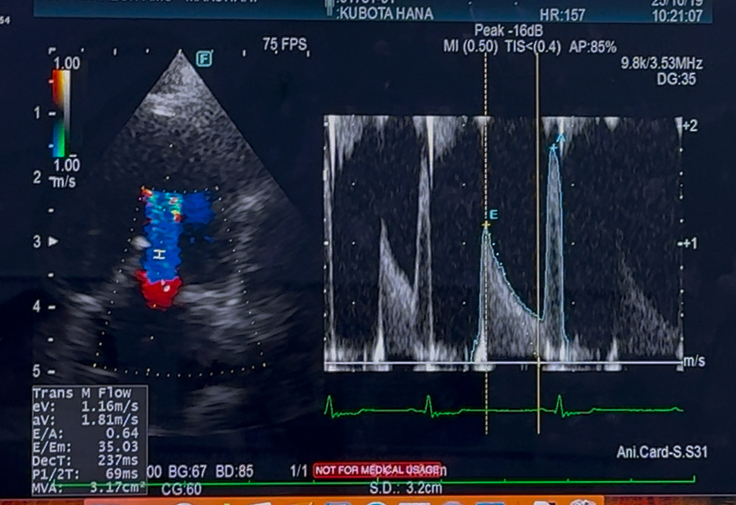

先日心臓手術後2年2ヶ月検診でした

心臓の方は

年齢的なものも相まって少し悪化がみられましたが

今すぐに何かしなければいけないと言う事はありませんでしたが

抗血栓薬は、まだ内服継続となりました